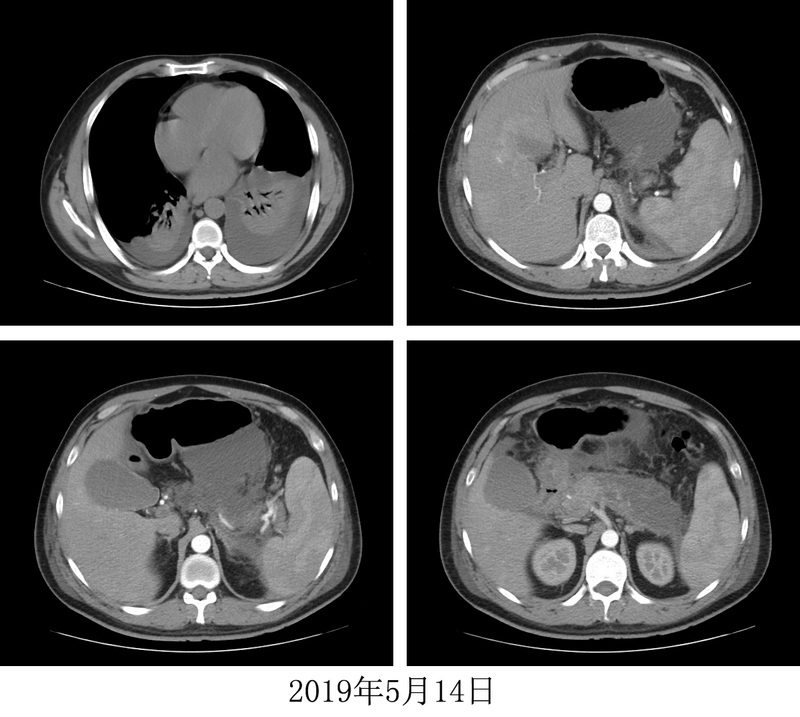

一、患者病歷摘要:患者聚餐飲酒后因“腹痛”于2019年5月3日在“滑縣中心醫(yī)院”就診,診斷為“急性胰腺炎”,次日轉入滑縣人民醫(yī)院,腹部CT提示急性壞死性胰腺炎,滲出液多;診斷為“重癥胰腺炎”,治療過程中,出現(xiàn)“腎功能衰竭”,行血液透析1次,因腹腔積液行腹腔引流管置入術,于2019年5月11日轉入我院ICU,于5月14日置入鼻腸營養(yǎng)管,在ICU積極綜合治療4天,病情難以控制,ICU結合外科意見,擬行手術治療,后院長指示中西醫(yī)結合介入治療,故于2019年5月15日轉入我科(消化內科)。轉入我科時,帶鼻腸營養(yǎng)管、腹腔引流管、右側鎖骨下中心靜脈導管及留置尿管,結合血液常規(guī)、生化、腹腔引流液、細菌學等指標及胸腹部影像學(彩超、CT)檢查,患者西醫(yī)診斷明確:急性重癥胰腺炎,并發(fā)一系列復雜情況:胰腺廣泛壞死、急性胰周液體/壞死性積聚(直徑超過10cm)、廣泛腹腔內滲出、腹腔感染并腹膜炎、雙側胸腔積液、肺部感染、雙下肺實變、低蛋白血癥、凝血功能障礙。急性重癥胰腺炎,就像在腹腔內引發(fā)了連環(huán)爆炸,初次爆炸后,會在腹腔埋下一系列的連環(huán)炸彈,比如最難處理的急性胰周液體/壞死性積聚,如果處理不好,將會形成棘手的胰腺假性囊腫/包裹性壞死。如何拆除這些腹腔內的炸彈,是考驗臨床大夫技術水平的難題。處理這種難題,除了積極的抗感染、抑酸、抑制胰酶等綜合治療之外,我們考慮的并不是有創(chuàng)的內鏡、介入及手術處理,最主要的盡早的給予中醫(yī)藥介入治療。圖1患者2019年5月14日胸腹部CT二、中醫(yī)辨證施治:從中醫(yī)角度考慮:患者主癥為口苦、發(fā)熱、腹脹、腹痛、不能進食、大便為稀水樣(雖有大便,但考慮主要是腹腔感染,腸粘膜滲出所致,并未排出實質性糞便,還是大便不暢),中上腹壓痛明顯(按之心下滿痛),脈弦數(shù)。六經(jīng)辨證考慮為少陽陽明合病,主方為大柴胡湯;舌象:舌質暗紅,苔厚膩,為痰濕及血瘀互結之象;整體考慮為少陽陽明合病并痰瘀互結證,方證辨證為:大柴胡湯、小陷胸湯、桂枝茯苓丸合方,大柴胡湯瀉熱通腑,小陷胸湯清熱祛痰散結,桂枝茯苓丸活血化瘀。處方:柴胡15g黃芩9g姜半夏15g枳實15g白芍15g生大黃(后下)6g黃連5g全瓜蔞20g桂枝10g茯苓20g桃仁10g赤芍15g牡丹皮15g生姜3片大棗4枚,每日1劑,水煎服。患者5月16日開始口服中藥,服藥后患者排出較多成形便并有較多粘液??诳?、發(fā)熱、腹脹、腹痛均快速緩解。服藥4天后,于5月20日復查胸腹部CT:雙側胸腔積液明顯減少,急性胰周液體/壞死性積聚明顯減少,腹腔內滲出明顯吸收。遂拔除腹腔引流管,開始經(jīng)口進食,減少腸內營養(yǎng),停用奧曲肽,繼續(xù)抗感染治療,效不更方,繼續(xù)口服中藥?;颊呓?jīng)口進食后無腹脹、腹痛等不適,于5月23日拔出鼻腸營養(yǎng)管,完全經(jīng)口進食。圖2患者2019年5月20日胸腹部CT口服中藥11天后,5月27日復查胸腹部CT:雙側胸腔積液及雙下肺實變均明顯吸收,胰周液體/壞死性積聚較5月14日減少約85-90%。血常規(guī)、肝腎功能、凝血功能、電解質、血糖、CRP、降鈣素原、脂肪酶、淀粉酶均正常,拔除右側鎖骨下中心靜脈導管,至此患者全身置入管道全部拔除,停用抗菌藥物,繼續(xù)口服中藥觀察。患者進食可,睡眠可,活動正常,無明顯不適,于5月30日出院。囑繼續(xù)口服中藥,3周后復查。圖3患者2019年5月27日胸腹部CT圖4患者中醫(yī)藥介入后治療過程中舌象動態(tài)變化三、思考:臨床中,部分急性胰腺炎患者會出現(xiàn)胰周液體積聚,少量的液體積聚是會吸收的。但是在急性重癥/壞死性胰腺炎患者中,急性壞死性積聚是大多數(shù)患者的自然病程,壞死面積越大則死亡率越高,如果出現(xiàn)了大于5-6cm的急性胰周液體/壞死性積聚,那么強烈提示這個液體/壞死性積聚會持續(xù)存在,進行性發(fā)展,3-4周后,則成為胰腺假性囊腫/或包裹性壞死。臨床上對于這種急性重癥胰腺炎的局部并發(fā)癥大面積急性胰周壞死性積聚的處理,缺乏有效的無創(chuàng)處理辦法,目前的指南多是推薦內鏡、介入或者手術處理。我們在臨床工作中,對于復雜難治消化病,采用中西醫(yī)病證結合治療,屢獲奇效。此例急性重癥胰腺炎的中醫(yī)藥治療經(jīng)過,再次讓我們領略了仲景之術的博大精深,中醫(yī)藥在急危重癥患者的治療中大有可為!現(xiàn)在好多人都認為,慢性病調理體質找中醫(yī),如果是急危重癥,好像和中醫(yī)都沒有什么關系,這是令人嘆息的現(xiàn)象!中國工程院院士、著名腫瘤外科專家湯釗猷在其新作《西學中,創(chuàng)中國新醫(yī)學》中,結合自己對西醫(yī)的客觀認識,提出了對中西醫(yī)結合的見解:“創(chuàng)中國新醫(yī)學”的核心是中西醫(yī)結合,實現(xiàn)中西醫(yī)結合的關鍵是西醫(yī)學習中醫(yī)?,F(xiàn)在是多學科協(xié)作時代,沒有哪一個學科可以很自信的說可以獨自解決患者的病痛,純粹的西醫(yī)現(xiàn)代醫(yī)學技術在很多臨床復雜難治情況的處理中,已進入瓶頸期,雖能診斷清楚,卻沒有有效處理辦法,著實令人尷尬。我們在臨床工作中發(fā)現(xiàn),急危重癥的處理,中醫(yī)藥的介入越早,病人越能獲得更好的臨床結局。